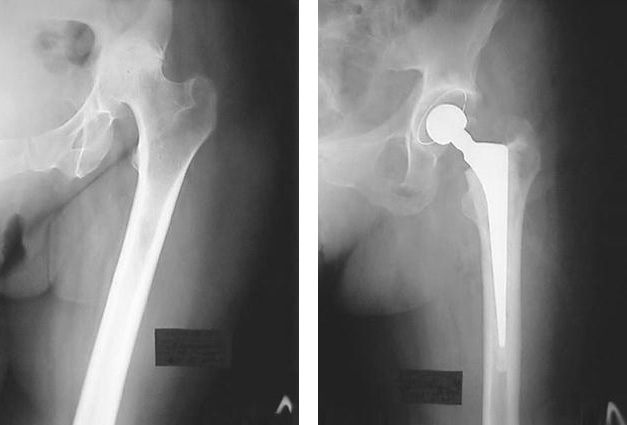

Томограмма позволяет увидеть на нескольких срезах изображение всех компонентов тазобедренного сустава и окружающих тканей.

Многослойное изображение МРТ — это высококачественное и детализированное представление анатомии органов. Оно позволяет увеличивать отдельные участки и исследовать мелкие структуры, такие как нервные волокна и кровеносные сосуды. МРТ также помогает выявлять усталостные переломы, гематомы и ранние стадии артрита, которые не всегда можно обнаружить с помощью обычного рентгена.